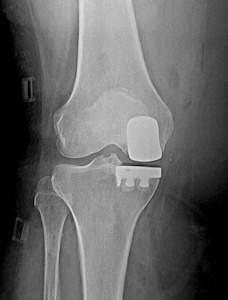

Eklemdeki aşınması dizin sadece sınırlı bir bölgesinde olan hastalarda unikondiler protezler tercih edilebilir. Hasta yaşının 60 ve üzeri olması istenir, ancak son yıllarda 50’li yaşlardaki hastalarda da unikondiler protezler güvenle uygulanmaktadır. Eklemdeki aşınma sadece bir bölgede olmalı, dizin geri kalanındaki eklem kıkırdağı, menisküsler, çapraz bağlar ve yan bağlar sağlam olmalıdır. Dizde şekil bozukluğu varsa (içe ya da dışa doğru eğrilik), bu muayene sırasında düzeltilebilir olmalıdır. Dizinde yaygın kıkırdak aşınması veya romatoid artrit gibi yaygın romatizmal hastalığı olan kişilerde unikondiler protezler uygun değildir. Osteonekroz adı verilen, dizin bir bölgesindeki damarların tıkanması sonucu kemik ölümü ve çökme gelişen hastalarda da unikondiler protezler uygulanabilir (Resim 3). Bu sınırlamalar göz önüne alındığında dizinde artroz (kireçlenme, aşınma) olan hastaların yaklaşık % 15’inde unikondiler protez yapılabilir.Resim 3a,b: Resim 3: Dizinde osteonekroz olan bir hastada unikondiler protez uygulaması.